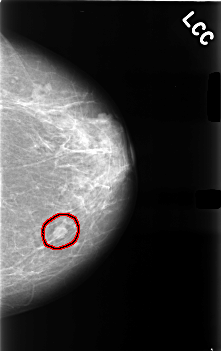

C_0491_1.LEFT_CC

LEFT_CC LINES 4560 PIXELS_PER_LINE 2864 BITS_PER_PIXEL 12 RESOLUTION 50 OVERLAY

FILE: C_0491_1.LEFT_CC.OVERLAY

TOTAL_ABNORMALITIES 1

ABNORMALITY 1

LESION_TYPE MASS SHAPE LOBULATED MARGINS CIRCUMSCRIBED

ASSESSMENT 4

SUBTLETY 5

PATHOLOGY BENIGN

TOTAL_OUTLINES 1

BOUNDARY